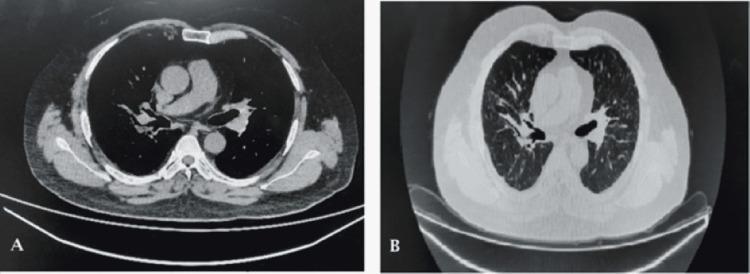

Nocardia is a rare gram-positive pathogen reported to cause infections in immunocompromised individuals. It usually involves the lungs but may also lead to abscess formation; cases of disseminated nocardiosis have also been reported. We are presenting a case of an Asian male who had sarcoidosis with pulmonary and skin involvement. The patient was on long-term immunosuppressive therapy with corticosteroids with good control of the disease. He developed a fever, weight loss, and right-sided chest pain. CT of the chest showed new nodular infiltrates. Worsening of sarcoidosis was suspected; the corticosteroid dose was increased and methotrexate was started. There was no favorable response to the increase in immunosuppressive therapy. Weight loss was followed by worsening shortness of breath and fluctuant swelling in the right lateral half of the chest. Bronchoalveolar lavage was done to rule out tuberculosis but it did not show any organism's growth. Ultrasound-guided needle aspiration from the abscess was done that showed growth of Nocardia species. Therapeutic dose co-trimoxazole (trimethoprim-sulphamethoxazole) was started as first-line therapy after confirming the organism's drug susceptibility pattern along with needle aspiration of the collection on the chest wall. Immunosuppressive agents were stopped. There was a good response to treatment with resolution of symptoms within two months. However, complete radiological recovery took 10 months. Co-trimoxazole (trimethoprim-sulphamethoxazole) therapy continued for two months after radiological recovery. Physicians, therefore, should keep Nocardia as an important differential diagnosis while treating the immunosuppressed population.

诺卡菌是一种罕见的革兰氏阳性病原体,据报道可在免疫功能低下的个体中引起感染。它通常累及肺部,但也可能导致脓肿形成;也有播散性诺卡菌病的病例报道。我们报告一例患有结节病且累及肺部和皮肤的亚洲男性病例。该患者长期接受糖皮质激素免疫抑制治疗,疾病控制良好。他出现发热、体重减轻和右侧胸痛。胸部CT显示有新的结节状浸润影。怀疑结节病病情恶化;增加了糖皮质激素剂量并开始使用甲氨蝶呤。免疫抑制治疗增加后未见好转。体重减轻后,呼吸急促加重,右侧胸部外侧出现波动性肿胀。进行支气管肺泡灌洗以排除结核病,但未发现任何微生物生长。对脓肿进行超声引导下针吸活检,结果显示诺卡菌生长。在确定微生物的药敏模式后,开始使用治疗剂量的复方新诺明(甲氧苄啶-磺胺甲恶唑)作为一线治疗,并对胸壁的积液进行针吸。停用免疫抑制剂。治疗反应良好,症状在两个月内缓解。然而,影像学完全恢复需要10个月。影像学恢复后,复方新诺明(甲氧苄啶-磺胺甲恶唑)治疗持续了两个月。因此,医生在治疗免疫抑制人群时应将诺卡菌作为重要的鉴别诊断。